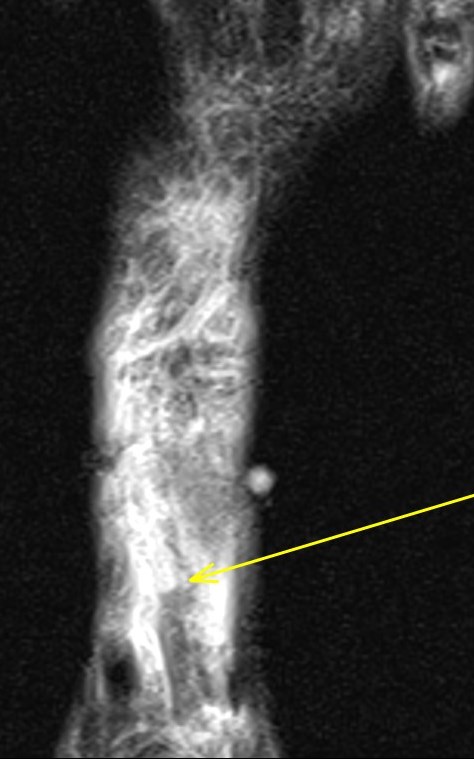

Figure 1 for case Extensor hallucis longus tendon ( RID3188 ) laceration

Figure 1

You can see the cleanly lacerated tendon edges nicely (arrows)